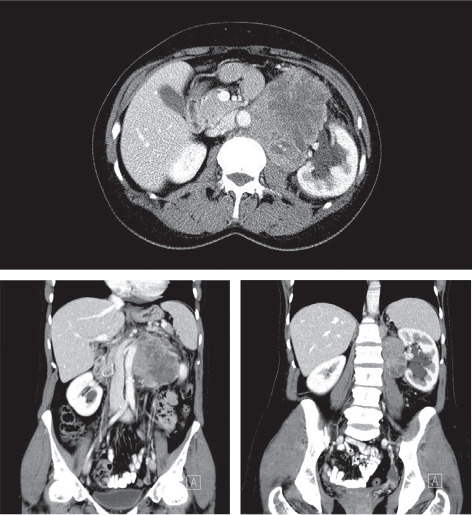

血管生成性平滑肌肉瘤(Angiogenic平滑肌肉瘤,LMS)是一种软组织肉瘤,主要发生在下腔静脉(IVC),超过50%的病例发生,肾静脉的LMS极为罕见。我们报告一例原发性左肾静脉LMS。病例报告:一名73岁女性,既往有高血压病史和左侧结肠腺癌,表现为间歇性左侧疼痛。影像学显示左侧主动脉外侧有一个大肿块。剖腹探查证实左肾门周围有多结节性肿瘤,需要行左肾全切除术。病理检查为2级LMS。患者术后恢复良好,无并发症。讨论:lms,尤其是血管源性lms,是一种罕见的侵袭性恶性肿瘤。尽管表现隐匿,但它们主要出现在女性身上,通常是成年人,而且经常出现在左侧。由于非特异性症状和影像学表现,诊断具有挑战性。手术切除仍然是治疗的基石,完全切除提供更好的结果。预后较差,特别是较大的肿瘤,部分切除和高度病变。辅助治疗的疗效尚不确定。结论:肾静脉LMS是一种罕见的疾病,诊断和治疗具有挑战性。根治性手术切除仍是主要治疗方法,但预后不佳,特别是在高危病例中。需要进一步的研究来优化这种罕见恶性肿瘤的治疗策略。

Introduction: Angiogenic leiomyosarcoma (LMS), a soft tissue sarcoma, primarily occurs in the inferior vena cava (IVC) in over 50% of cases, with renal vein LMSs being exceedingly rare. We present a case of primary LMS of the left renal vein. Case Report: A 73-year-old woman with a history of hypertension and prior left colon adenocarcinoma presented with intermittent left flank pain. Imaging revealed a large left latero-aortic mass. Exploratory laparotomy confirmed a multinodular tumor around the left renal hilum, necessitating en bloc resection with left nephrectomy. Pathological examination identified it as a grade 2 LMS. The patient recovered well postoperatively with no complications. Discussion: LMSs, especially of vascular origin, are rare and aggressive malignancies. Despite their insidious presentation, they predominantly manifest in women, typically adults, and often on the left side. Diagnosis is challenging due to nonspecific symptoms and imaging findings. Surgical resection remains the cornerstone of treatment, with complete resection offering better outcomes. Prognosis is poor, particularly with larger tumors, partial resection, and high-grade lesions. Adjuvant therapy's efficacy is uncertain. Conclusion: LMS of the renal vein is a rare entity with challenging diagnosis and management. Radical surgical resection remains the mainstay, but prognosis is guarded, especially in high-risk cases. Further research is needed to optimize treatment strategies for this rare malignancy.